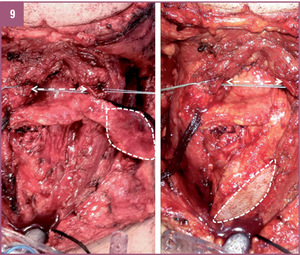

Zaplanowanie, wytworzenie, kształtowanie oraz implantacja zmodyfikowanego mikronaczyniowego płata małżowiny usznej opartego na naczyniach skroniowych.

A.M.: Tak, wspólnie uznaliśmy, że opracowanie takiej metody byłoby bardzo skuteczne i pomocne dla cierpiących na średnio lub wysoko zaawansowaną chorobę nowotworową nagłośni lub też średnio zaawansowanego raka krtani obejmującego nagłośnię. Doszliśmy do wniosku, że skoro do tej pory stosowano wiele nieskutecznych metod, nadszedł czas na wykorzystanie trójwymiarowej struktury odpowiadającej nagłośni i pochodzącej z ludzkiego ciała. Założyliśmy więc, że możemy wykorzystać zmodyfikowany fragment małżowiny usznej na naczyniach skroniowych z elementami skóry okolicy przed-, za- i nadusznej. Chodziło nam o to, by te elementy skórne odtwarzały boczne ściany gardła i część górną krtani, która również jest resekowana w przypadku raka nagłośni. Fragment małżowiny usznej z chrząstką w środku mógłby zatem po modyfikacji stanowić element elastyczny odpowiadający kształtowi i wielkości nagłośni. Liczne zabiegi przeprowadzone na zwłokach utwierdziły nas w przekonaniu, że wykonanie takich rekonstrukcji jest możliwe. Po kwalifikacji i przygotowaniu chorych na raka nagłośni w stopniu zaawansowania T2 i T3 z naciekiem na nasadę języka (nie większym niż 1-2 cm, gdzie kończy się możliwość rozsądnej rekonstrukcji), postanowiliśmy wykorzystać tę właśnie technikę.

CHARAKTERYSTYKA PRZYPADKU